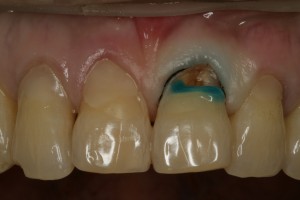

치료를 시작하기로 하였습니다. 치료 중의 임상사진입니다.

레진이라는 재료로 치경부를 매끈하게 채워 놓기 위하여 잇몸사이에 검은 실을 넣은 것을 볼 수 있습니다.

사진에서 보이는 파란색 물질은 레진을 채워 넣기 전에 하는 술식입니다.